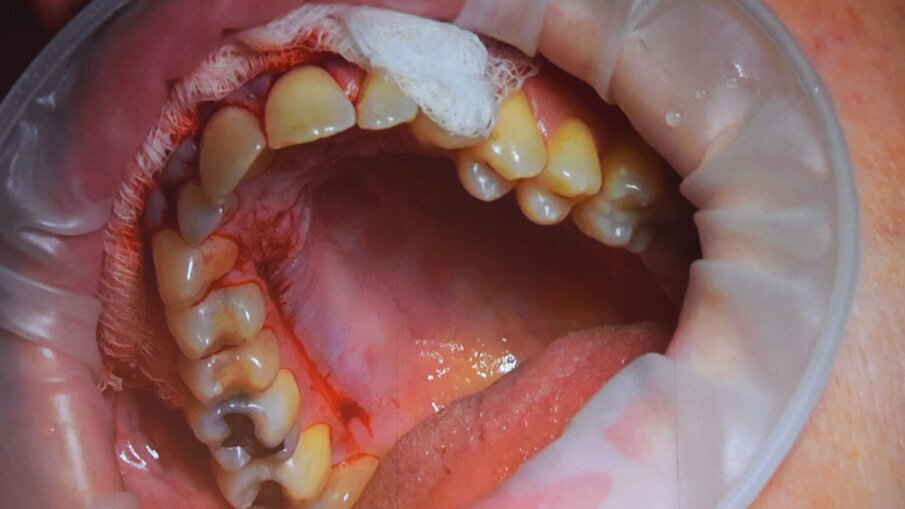

On Thursday morning, Hall D was packed with attendees eagerly awaiting the livestreaming of two mucogingival surgeries that were to be performed to cover multiple gingival recessions.

The live surgeries ran in parallel, allowing attendees to follow the critical steps of each method.